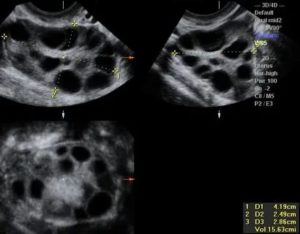

Важно! В большинстве случаев мультифолликулярные яичники у пациенток обнаруживается случайно при прохождении УЗИ. Обычно такие железы имеют обычные размеры, их капсула не изменена. Количество пузырьков не превышает 10, диаметр их колеблется от 4 до 8 мм.

Врач ультразвуковой диагностики при проведении ультразвукового обследования без труда определяет МФЯ. Их основные эхографические признаки мультифолликулярных яичников:

- Размер яичников незначительно превышает норму;

- Эхогенность (способность ткани по-своему отражать ультразвуки) у яичников меньше, чем у матки;

- Множественные (более 20) антральные фолликулы (структуры с высокой вероятностью дозревания), их размер не превышает 9 мм;

- Доминантный фолликул не имеет утолщенной капсулы;

- Расположение антральных фолликулов диффузное (разбросанное).

- Размер яичников – у мультифолликулярных яичников объем немного больше, чем обычно. Длина фолликула при СПКЯ составляет более 40 мм, с нормой 34-37 мм.

- Фолликулы – в обоих случаях наблюдаются множественные структурные элементы. С МФЯ их диаметр составляет не более 9 мм, а при СПКЯ они значительно превышают норму. Капсула фолликула при поликистозе сильно утолщена, что препятствует выходу яйца и провоцирует рост фолликулярных кист.